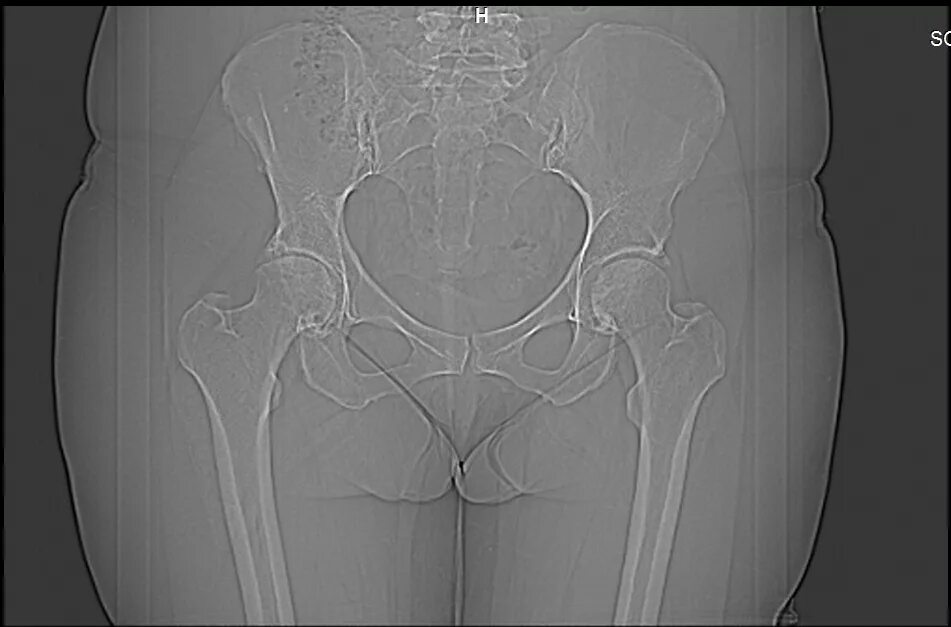

Коксартроз тазобедренного 1 стадии